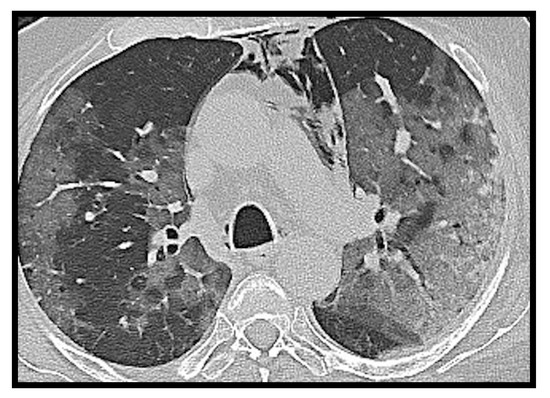

2.6. Cavitation

Cavitation is quite rare in viral pneumonia and consequently also in SARS-CoV-2 and MERS-CoV pneumonias [21,22,23].

Zoumut et al. [24] investigated the development of lung cavitation in patients with severe COVID-19 disease treated in ICU; a frequency of 11% was detected. They assumed that cavitation was due to several factors such as bacterial and fungal coinfection, immunosuppressive effects of glucocorticoids and tocilizumab, inflammatory state induced by SARS-CoV-2, and thrombotic diathesis (Figure 6). This study also reported that lung cavitation in patients with severe COVID-19 lung disease can occur and is associated with secondary complications, such as hemoptysis and pneumothorax, conferring a poor prognosis.

Figure 6. Axial CT image of a 70-year-old female patient. Gross parenchymal consolidation with central excavation suspected for superinfection is evident in the anterior segment of the right upper lobe. In addition, reinforcing suspicion of superinfection, the study was negative for pulmonary embolism.